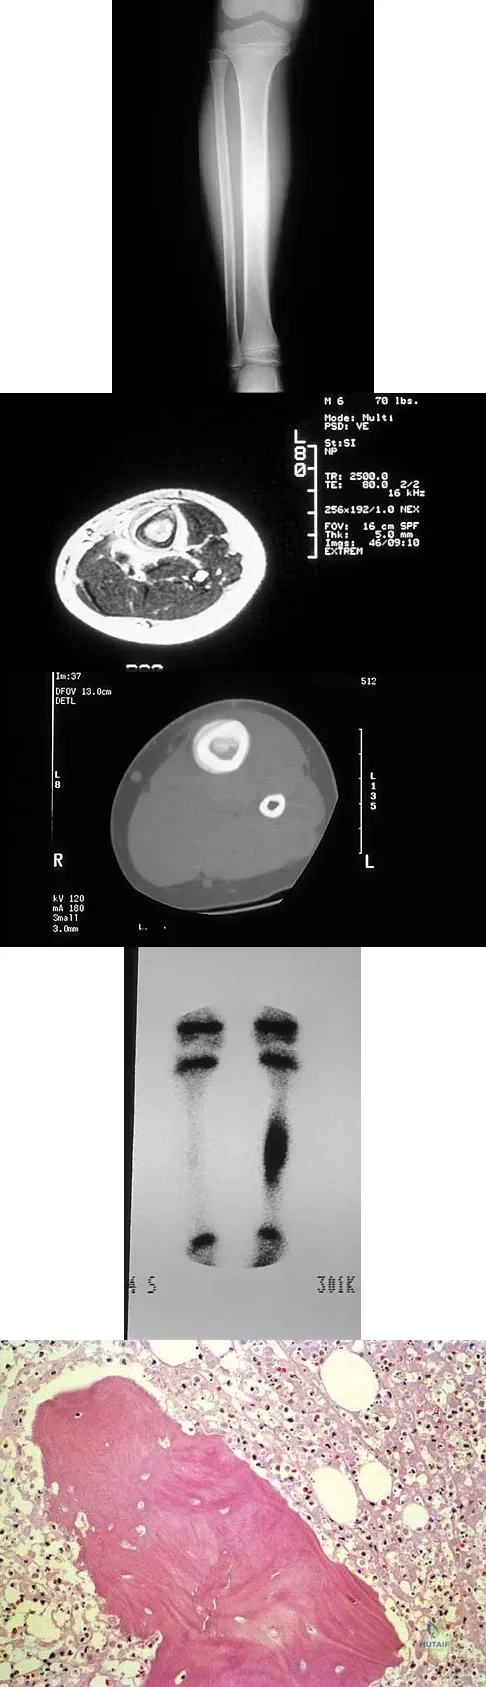

A 6-year-old boy has leg pain. A radiograph, MRI, CT, and bone scans, and a biopsy specimen are shown in Figures 14a through 14e. What is the most likely diagnosis?

Explanation